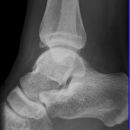

Sprunggelenk

Weber C + dorsales Volkmann

Trimalleoläre